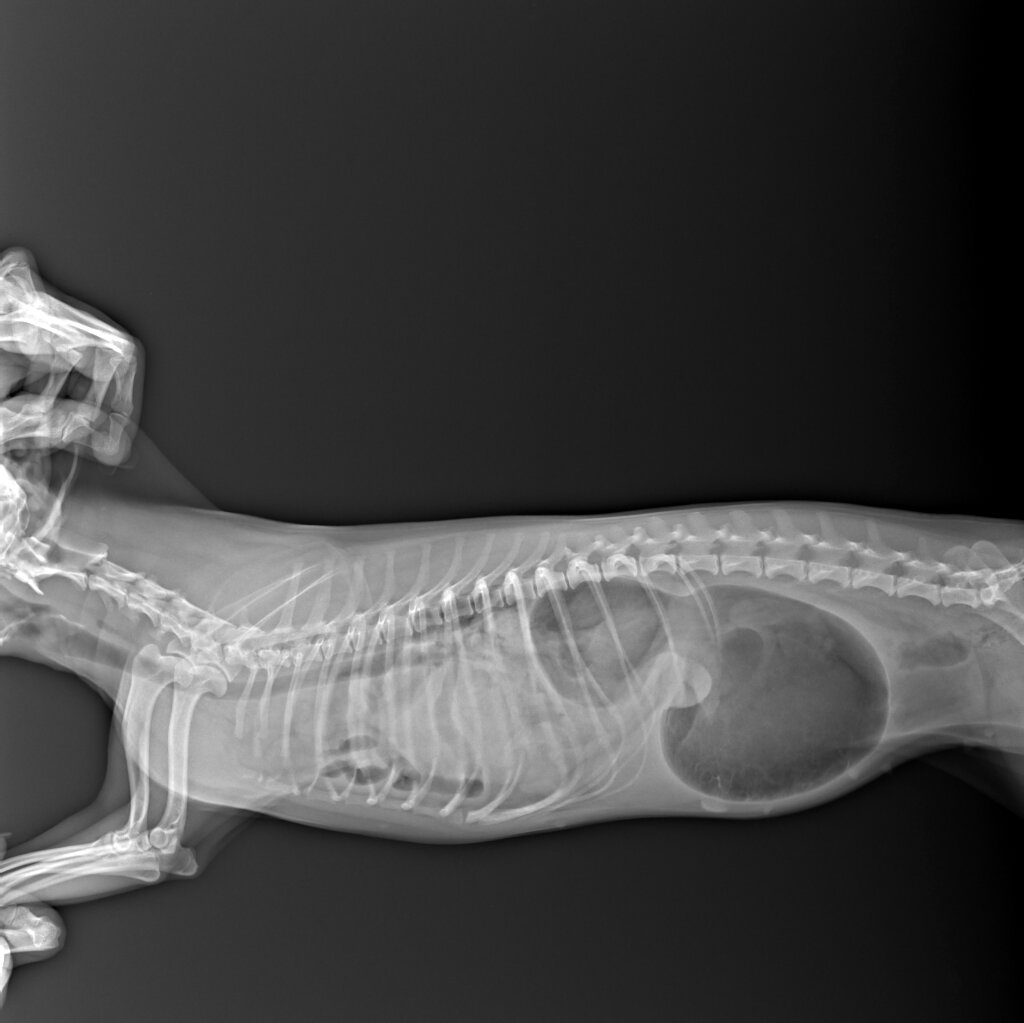

Мы сделали рентген и увидели следующее: на снимке даже не видно легких, так как немалая часть внутренних органов мигрировала в грудную клетку.

Спойлер: во время операции мы обнаружили к грудной клетке 1/3 часть желудка, сложенную пополам селезенку, левую почку, левый яичник, часть кишечника.